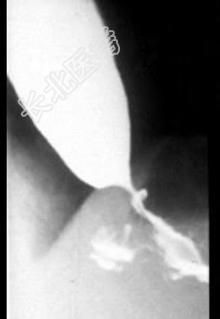

- 单项选择题患者,女性, 50岁,进行性吞咽困难半年, 现仅能进食水,入院行X线钡餐检查, 结果如图所示,最可能的诊断是 ( )

A、食管憩室

B、食管平滑肌瘤

C、贲门失弛症

D、食管癌

E、以上均不正确